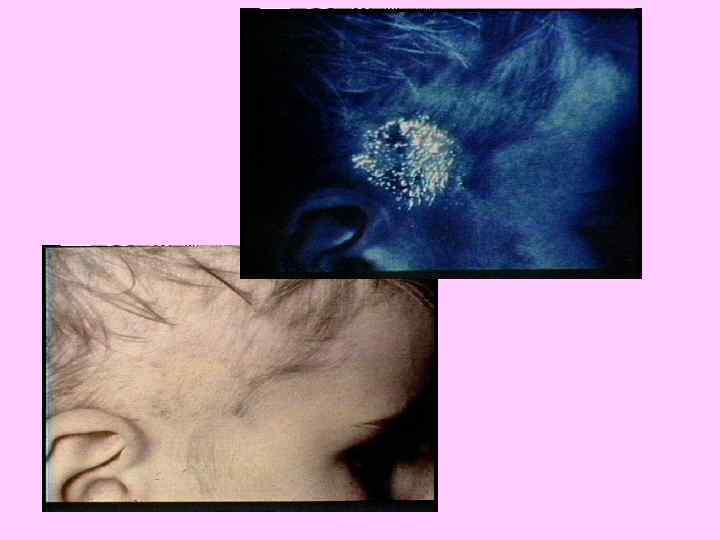

КЛАССИФИКАЦИЯ ГРИБКОВЫХ ЗАБОЛЕВАНИЙ ПОВЕРХНОСТНЫЕ МИКОЗЫ ТРИХОФИТИЯ МИКРОСПОРИЯ ЭПИДЕРМОФИТИЯ КАНДИДАМИКОЗ Дерматофитозы (около 40 видов возбудителей) ГЛУБОКИЕ И СИСТЕМНЫЕ МИКОЗЫ КАНДИДАМИКОЗ ГИСТОПЛАЗМОЗ КРИПТОКОККОЗ КОКЦИДОИДОЗ АСПЕРГИЛЛЕЗ БЛАСТОМИКОЗ

ДЕРМАТОФИТЫ «АНТРОПОФИЛЬНЫЕ» Microsporum audounii Trichophyton rubrum Trichophyton schoenlenii «ЗООФИЛЬНЫЕ» Microsporum canis «ГЕОФИЛЬНЫЕ» Microsporum gypseum (трихифития)